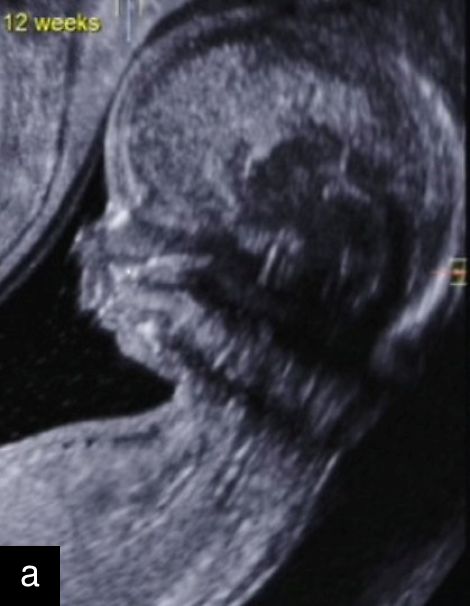

5

Sagittal ultrasound images, showing normal nuchal translucency (NT) at 12 weeks (a) and increased NT at 13 weeks (b).